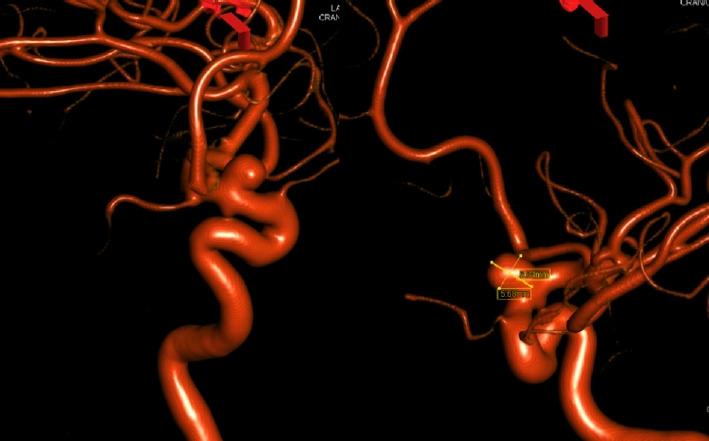

The Pipeline Embolization Device (PED) is a flow-diverting intraluminal device that is approved for use in adults 18 years or older with internal carotid artery aneurysms. However, it can also be used off-label in pediatric patients with aneurysms that cannot be resolved with traditional endovascular treatments. Herein, we present two cases of flow diversion in the pediatric population with complete obliteration of the aneurysm and excellent outcomes. Flow diversion has been shown to be a safe endovascular option in treating complex aneurysms in children. Larger-sized, multicenter trials are encouraged to compare outcomes between flow diversion and other aneurysm treatment options given the rarity of pediatric aneurysms.